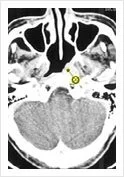

Early NPC on Axial CT Scan

Early NPC is rare as it is in a silent area and symptoms present late in the disease.